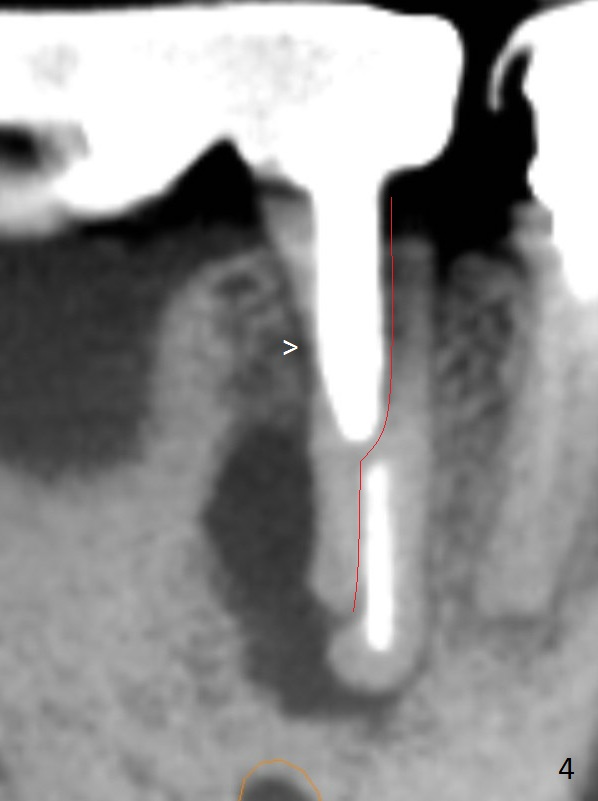

A 50-year-old man has pain and swelling buccal to the tooth #29 with large distal radiolucency (Fig.1 *).  The bridge will be sectioned between #30 and 31.  The mesial segment of the bridge is expected to separate from #29 post space; the mesial abutment is presumed to have vertical fracture (Fig.4 red line or root perforation due to oversized post (>)).  After intraligamental injection, extraction and no Antibiotic treatment, a narrow long implant (Fig.6,7: 3.8x15 or 13 mm) will be placed as mesial and lingual as possible to avoid the buccal bony defect (Fig.5 >; repaired with Osteotape or PRF membrane) and the Mental Loop (Fig.1 >).

The ridge at #30 is pointed (Fig.2) and going to be resected (Fig.3 black area) to receive a narrow, short implant (3.8x8.5 mm).   A splinted immediate provisional will be fabricated following placement of a 4.5x4(5) mm abutment at #30 (Fig.2,3).  Take Alginate impression when the patient arrives in case the tooth #31 is also non-salvageable.